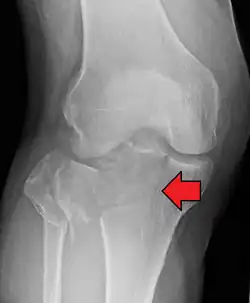

A tibial plateau fracture seen on X-ray

In all injuries to the tibial plateau radiographs (commonly called x-rays) are imperative. Computed tomography scans are not always necessary but are sometimes critical for evaluating degree of fracture and determining a treatment plan that would not be possible with plain radiographs.[10] Magnetic Resonance images are the diagnostic modality of choice when meniscal, ligamentous and soft tissue injuries are suspected.[11][12] CT angiography should be considered if there is alteration of the distal pulses or concern about arterial injury.